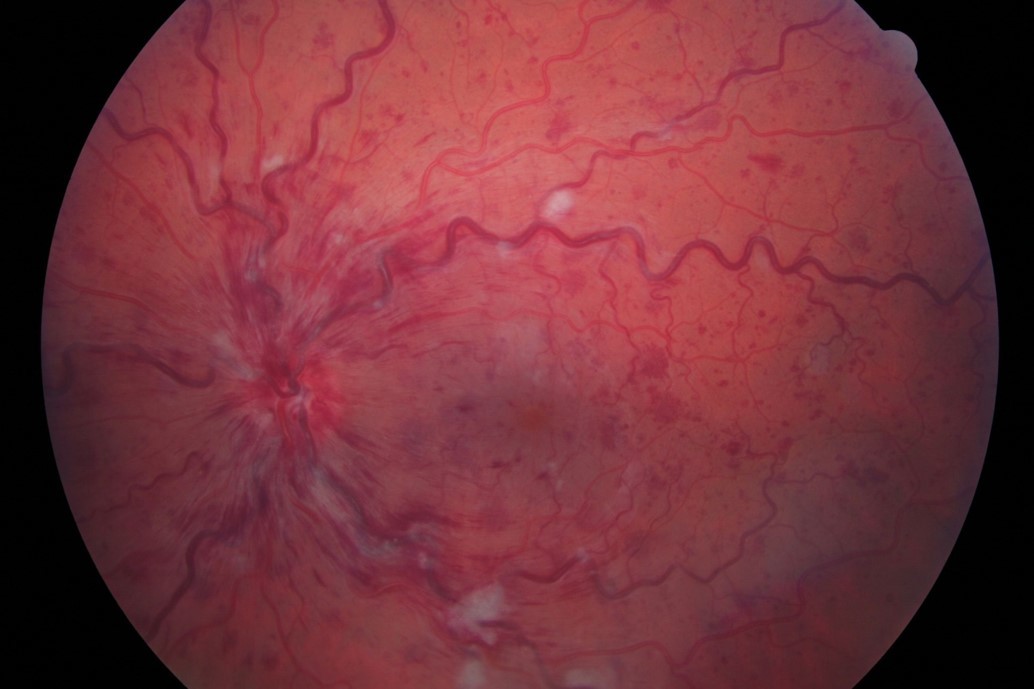

What signs on fundoscopy would indicate central retinal vein occlusion?

Retinal haemorrhages

Dilated tortuous veins

Disc swelling and macular swelling

What is the diagnosis here?

Central retinal vein occlusion

How is central retinal vein occlusion managed?

Treat systemic cause e.g. hypertension, glaucoma

Monitor: complications may arise if new vessels develop

Anti-VEGf